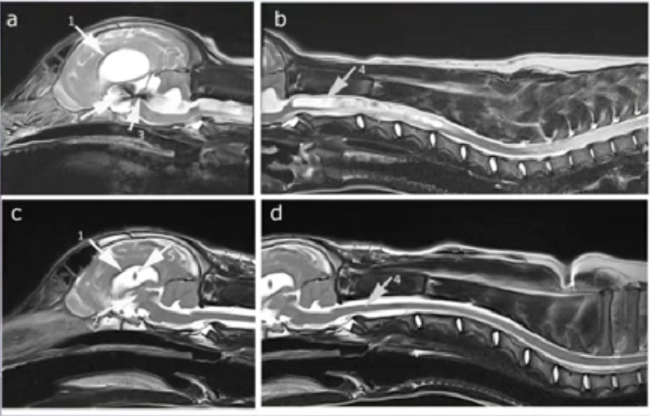

VP shunts have become a standard method of treating hydrocephalus in dogs. At the 2023 meeting of the British Veterinary Neurology Society, Dr. Ana Fernandez Cid reported on the successful insertion of a VPS for management of CM/SM in a cavalier. The series of MRI images below, courtesy of Dr. Rusbridge, show in (a) the arrow pointing to the enlarged ventricles, and in (b) a massive syrinx and developing pre-syrinx, prior to VP shunt surgery. In the post-operative MRI a month later, image (c) shows the two arrows pointing to the reduced size ventricles and the shunt within them. In (d), the arrow points to the completely collapsed syrinx and an almost normal spinal cord.